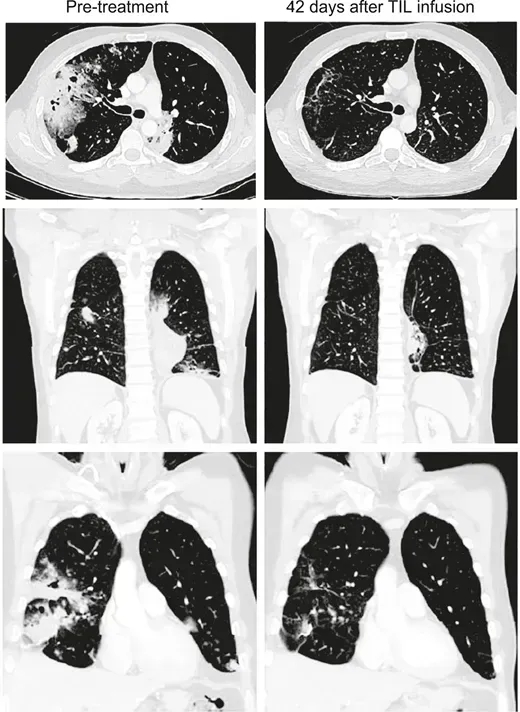

结果显示:肝切除术后2个月,所有肺转移灶完全消失,至今(48个月)仍保持无瘤状态(详见下图a、b)。

▲图源“Liver Cancer”,版权归原作者所有,如无意中侵犯了知识产权,请联系我们删除

结果显示:肝切除术后1个月,肺转移灶进展,右肺结节增大至25mm;接受TIL输注及常规抗PD-1治疗后,术后10个月肺病灶完全消失,至今24个月仍保持无瘤状态(详见下图c、d)。